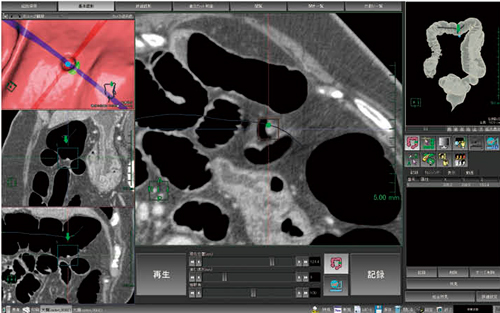

2)記録機能

当社の大腸解析では,発見した病変位置を記録することが可能である。あらゆる2D,3D画像上で位置がリンクしているため,どの画像からでもその病変を選択するだけでさまざまな表示方法で観察することが可能である(図8)。

図8 記録機能